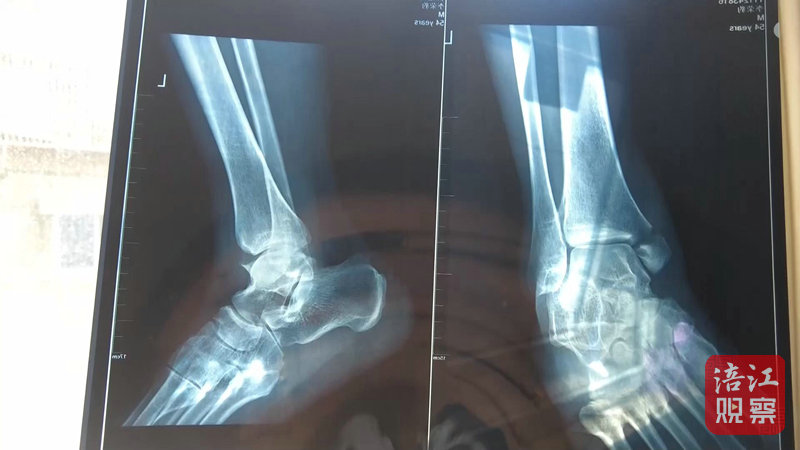

4月22日,記者來到綿陽市骨科醫(yī)院,病房內(nèi),李先生正在進(jìn)行術(shù)后上下床的康復(fù)訓(xùn)練。李先生的主治醫(yī)生介紹,李先生因左內(nèi)踝骨折入院,手術(shù)一周后傷口愈合良好,病情穩(wěn)定,目前已轉(zhuǎn)入康復(fù)科進(jìn)行康復(fù)功能鍛煉。